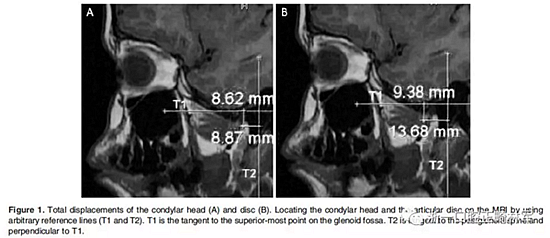

在生理休息位和另外三個位置獲得了四個咬合蠟型,這三個位置是水平前伸0mm時的HA1,水平前伸5mm時的HA2以及水平前伸7.5mm時的HA3。所有三個位置均保持垂直高度為5mm。病人分別將四個蠟型咬在嘴里,接受了5次連續(xù)磁共振掃描。外部標記的Frankfort水平面保持垂直于掃描臺。標記髁突頭和關(guān)節(jié)盤的位置,并在整個研究過程中對它們的位置變化進行描繪(Figure 1和2;1Table 1和2)。